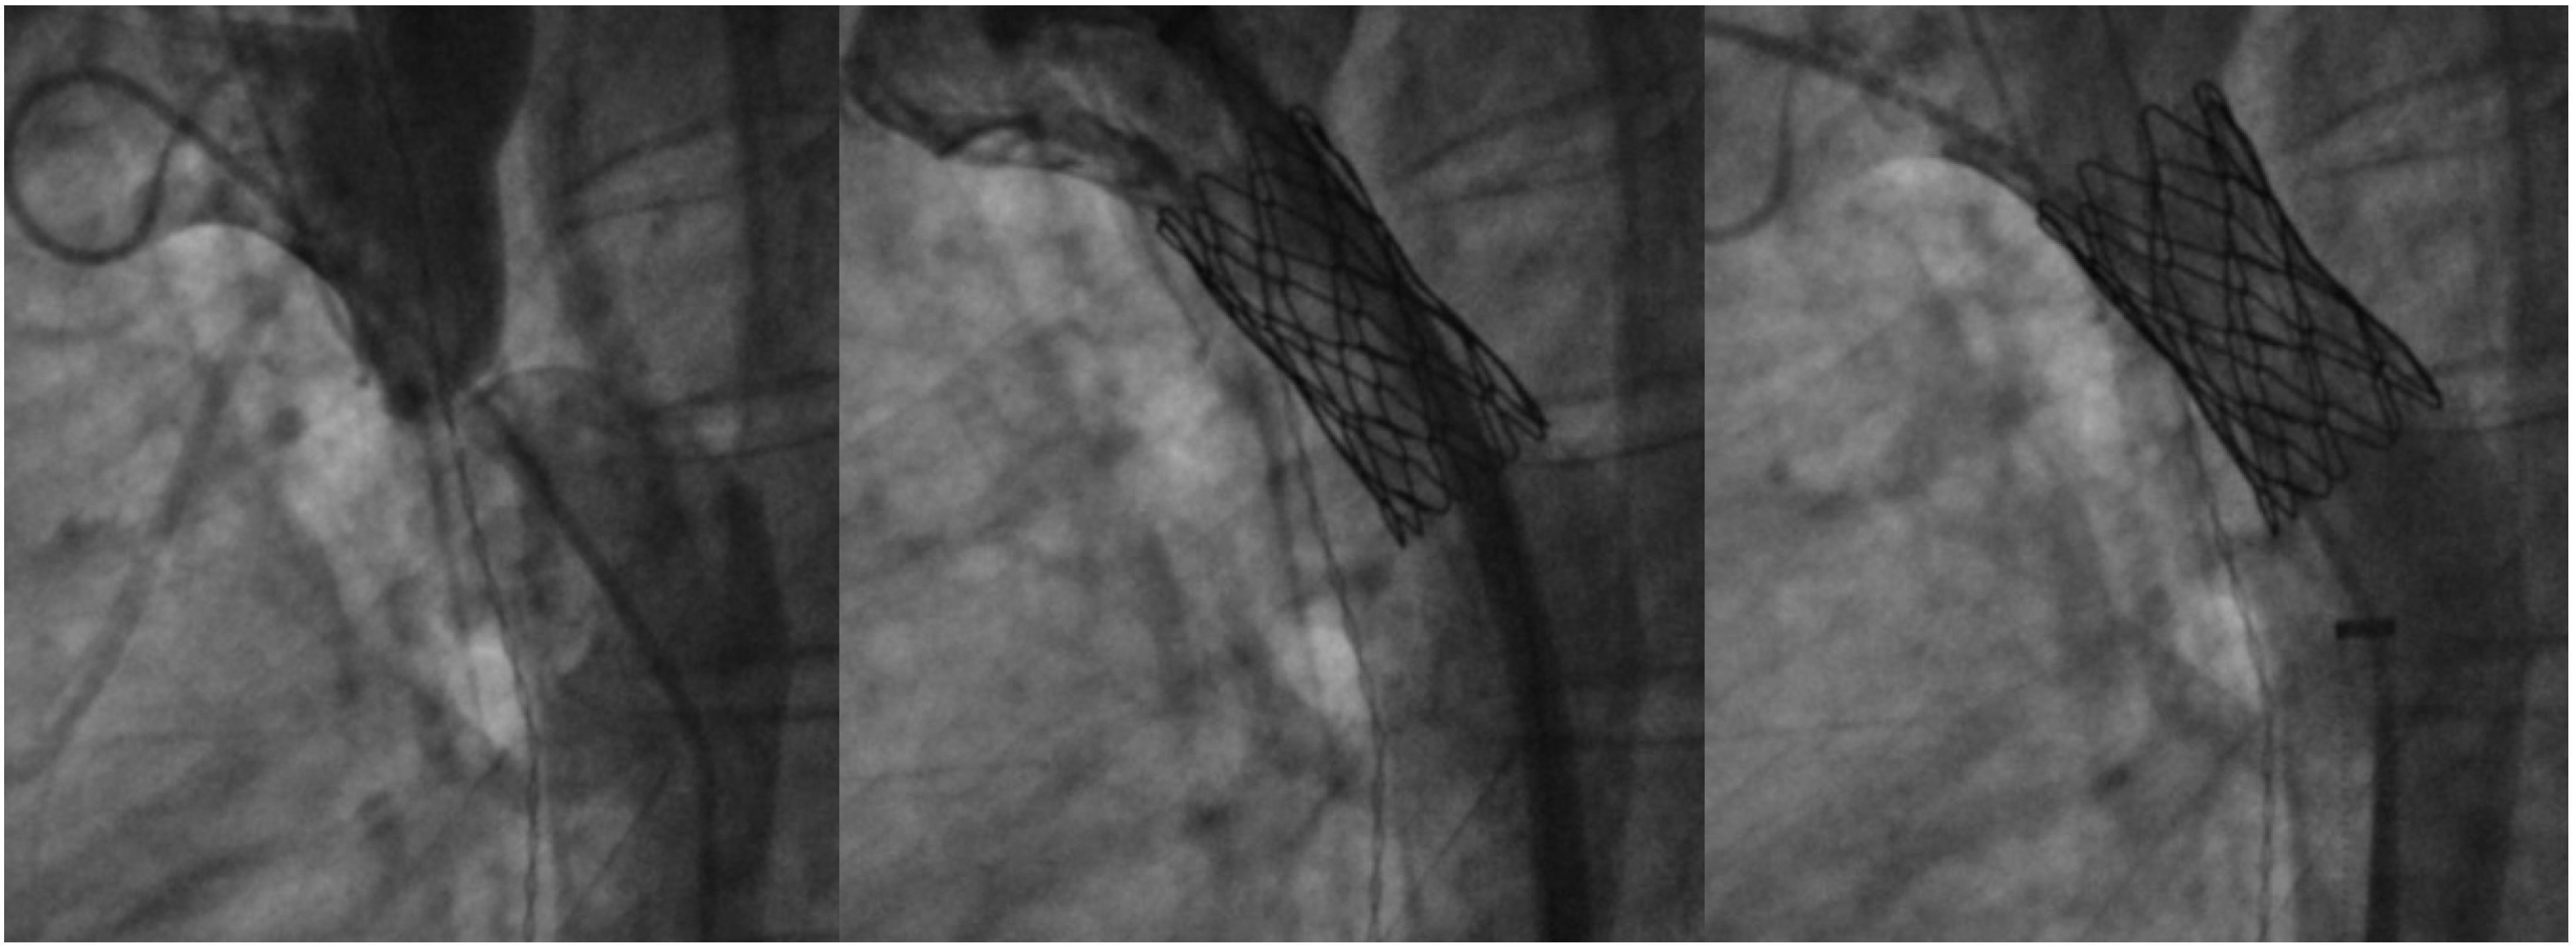

7. Coarctation of Aorta Stenting

- Salcher, M.; Naci, H.; Law, T.J.; Kuehne, T.; Schubert, S.; Kelm, M.; Morley-Fletcher, E.; Hennemuth, A.; Manset, D.; Mcguire, A.; et al. Balloon Dilatation and Stenting for Aortic Coarctation: A Systematic Review and Meta-Analysis. Circ. Cardiovasc. Interv. 2016, 9, e003153. [Google Scholar] [CrossRef]

- Golden, A.B.; Hellenbrand, W.E. Coarctation of the aorta: Stenting in children and adults. Catheter. Cardiovasc. Interv. 2007, 69, 289–299. [Google Scholar] [CrossRef]

- Hartman, E.M.J.; Groenendijk, I.M.; Heuvelman, H.M.; Roos-Hesselink, J.W.; Takkenberg, J.J.M.; Witsenburg, M. The effectiveness of stenting of coarctation of the aorta: A systematic review. EuroIntervention J. Eur. Collab. Work. Group. Interv. Cardiol. Eur. Soc. Cardiol. 2015, 11, 660–668. [Google Scholar] [CrossRef] [PubMed]

- Tyagi, S.; Singh, S.; Mukhopadhyay, S.; Kaul, U.A. Self- and balloon-expandable stent implantation for severe native coarctation of aorta in adults. Am. Heart J. 2003, 146, 920–928. [Google Scholar] [CrossRef] [PubMed]

- Egan, M.; Holzer, R.J. Comparing balloon angioplasty, stenting and surgery in the treatment of aortic coarctation. Expert. Rev. Cardiovasc. Ther. 2009, 7, 1401–1412. [Google Scholar] [CrossRef] [PubMed]

- Cheatham, J.P. Stenting of coarctation of the aorta. Catheter. Cardiovasc. Interv. 2001, 54, 112–125. [Google Scholar] [CrossRef]

- Kenny, D.; Margey, R.; Turner, M.S.; Tometzki, A.J.; Walsh, K.P.; Martin, R.P. Self-expanding and balloon expandable covered stents in the treatment of aortic coarctation with or without aneurysm formation. Catheter. Cardiovasc. Interv. 2008, 72, 65–71. [Google Scholar] [CrossRef]

- Holzer, R.J.; Gauvreau, K.; McEnaney, K.; Watanabe, H.; Ringel, R. Long-Term Outcomes of the Coarctation of the Aorta Stent Trials. Circ. Cardiovasc. Interv. 2021, 14, e010308. [Google Scholar] [CrossRef]